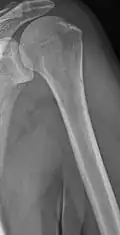

The diagnostic examination of a person with suspected multiple myeloma typically includes a skeletal survey. This is a series of X-rays of the skull, axial skeleton, and proximal long bones. Myeloma activity sometimes appears as "lytic lesions" (with local disappearance of normal bone due to resorption) or as "punched-out lesions" on the skull X-ray ("raindrop skull"). Lesions may also be sclerotic, which is seen as radiodense.[76] Overall, the radiodensity of myeloma is between −30 and 120 Hounsfield units (HU).[77] Magnetic resonance imaging is more sensitive than simple X-rays in the detection of lytic lesions. An MRI may supersede a skeletal survey, especially when vertebral disease is suspected. Occasionally, a CT scan is performed to measure the size of soft-tissue plasmacytomas. Nuclear Medicine Bone scans are typically not of any additional value in the workup of people with myeloma (no new bone formation; lytic lesions not well visualized on nuclear bone scan).

Humerus with multiple myeloma lesions -

Same humerus before, with just subtle lesions